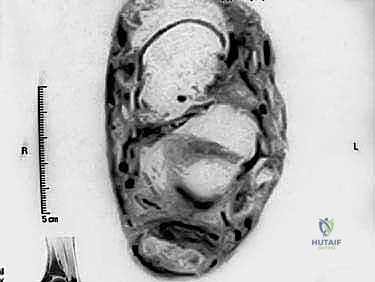

- التصوير بالرنين المغناطيسي (MRI): هو المعيار الذهبي والأداة الأقوى. يوفر صوراً ثلاثية الأبعاد وعالية الدقة تُظهر بدقة حجم التلف داخل الوتر، الأنسجة الندبية، حالة الجراب الزلالي، ومدى صلاحية وتر (FHL) لاستخدامه في الجراحة.

3. وتر العضلة الطويلة المثنية لإبهام القدم (FHL Tendon)

هنا يكمن السر الجراحي. العضلة الطويلة المثنية لإبهام القدم (Flexor Hallucis Longus) هي عضلة قوية تقع في عمق الساق الخلفية. يمر وترها خلف الكاحل وتحت القدم ليصل إلى إبهام القدم، ووظيفته الأساسية هي ثني الإصبع الكبير. يتميز هذا الوتر بأنه قوي جداً، طويل، وله مسار تشريحي يجعله قريباً جداً من وتر أخيل. الأهم من ذلك، أن عضلة (FHL) تنقبض في نفس المرحلة من دورة المشي التي تنقبض فيها عضلات الساق المرتبطة بوتر أخيل. لذلك، يعتبر هذا الوتر "المرشح المثالي" والمطابق حيوياً لتعويض وتر أخيل التالف.

لماذا نستخدم وتر العضلة الطويلة المثنية لإبهام القدم (FHL) تحديداً؟

عند إزالة الأجزاء التالفة من وتر أخيل، قد يتبقى أقل من 50% من الوتر السليم، وهو غير كافٍ لتحمل وزن الجسم. لذلك يجب "تعزيزه" بوتر آخر. يتم اختيار وتر (FHL) للأسباب الحيوية التالية:

1. القوة الميكانيكية: هو ثاني أقوى وتر في الساق بعد وتر أخيل.

2. التوافق الحركي: العضلة الخاصة به تعمل في نفس المرحلة الحركية (Phase-matched) مع عضلات الساق، مما يجعل إعادة التأهيل أسهل والمشي طبيعياً.

3. القرب التشريحي: يمر الوتر قريباً جداً من عظم الكعب، مما يسهل نقله جراحياً.

4. الإمداد الدموي: العضلة المرتبطة به توفر إمداداً دموياً ممتازاً للمنطقة، مما يسرع من شفاء وتر أخيل المتبقي.